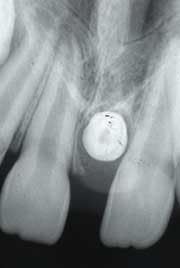

After a thorough clinical examination, four bite-wing radiographs and a panoramic film were ordered. In addition, a periapical film was ordered to examine the diastema area between the maxillary central incisors. Examination of the periapical radiograph revealed a dense tooth-like radiopacity surrounded by a radiolucent rim (see radiograph). The radiopacity was also apparent on the panoramic film.

As viewed on a dental radiograph, the mesiodens appears as a tooth-like radiopacity. This tooth-like radiopacity may appear rudimentary or conical in shape, or, resemble teeth normally found in the region. The size may vary from normal to miniature.

The diagnosis of a mesiodens is based on its radiographic appearance. On a good quality radiograph, the outline of a tooth and the radiolucent shadows of the pulp cavity and surrounding follicle are characteristic for the mesiodens.